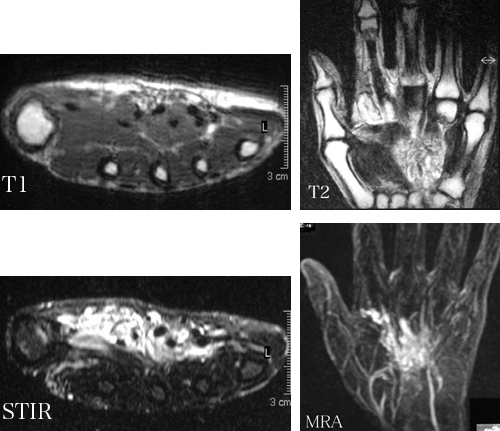

日々の症例 70 軟部の血管腫hemangioma。